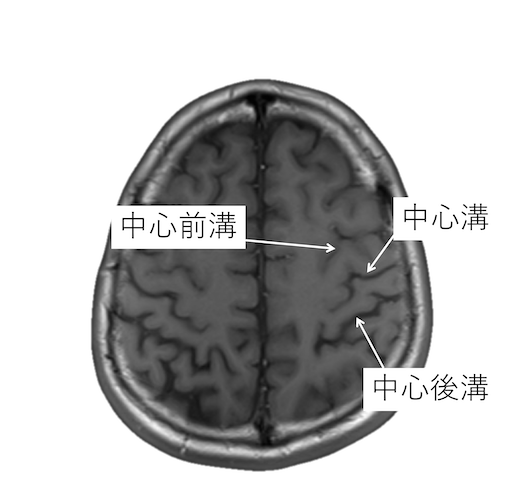

中心溝、中心前溝、中心後溝、中心前回、中心後回のMRI画像における解剖

主に脳梗塞診断などで重要な中心溝、中心前溝、中心後溝、中心前回、中心後回のMRI画像における解剖(CTでも使えます。)をご覧いただけます。

中心溝を同定する際には、以下の4つの原則があります。

・中心前溝は上前頭溝と、中心後溝は頭頂間溝と、連続するが、中心溝が連続する脳溝はない。

・中心後溝の内側端はY字型になり、帯状溝縁部(ちょび髭)は分岐に挟まれる。中心溝の内側端は帯状溝縁部(ちょび髭)のすぐ前にくる。

・脳回の前後幅は中心前回が後回より太い。

・中心前回の手指運動野は後方凸を示す(precentralknob sign)